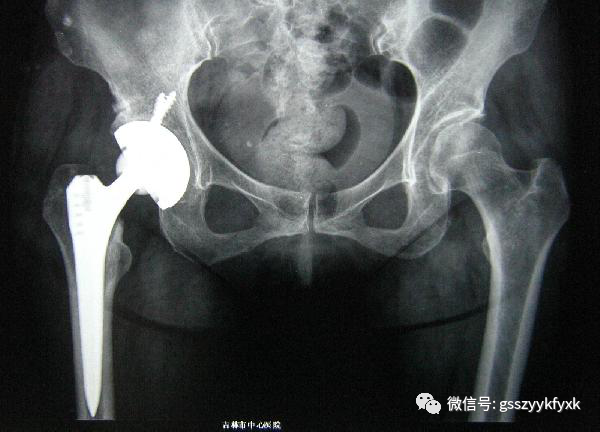

关节置换术是指用人工关节替代和置换病损关节。目前它已应用于治疗肩关节、肘关节、腕关节、指间关节 、髋关节、膝关节及踝关节等疾患,但以全人工髋关节及膝关节置换最为普遍。

人工髋关节手术适应症

1. 60岁以上的老年人在患髋关节骨性关节炎时,如果疼痛明显、功能障碍、关节间隙明显变窄均可考虑行全髋关节置换手术。2. 60岁以上的老年人股骨颈骨折,骨折明显移位,现已倾向于做全髋关节置换。3. 股骨头缺血性坏死。4. 类风湿性关节炎、强直性脊柱炎所致髋关节炎。此类患者多为较年轻的患者,因 不能忍受疼痛及关节活动受限给工作、学习、生活、婚姻带来的不便,也可考虑行全髋关节置换。5. 股骨头、股骨颈或髋臼肿瘤。6. 髋关节强直。